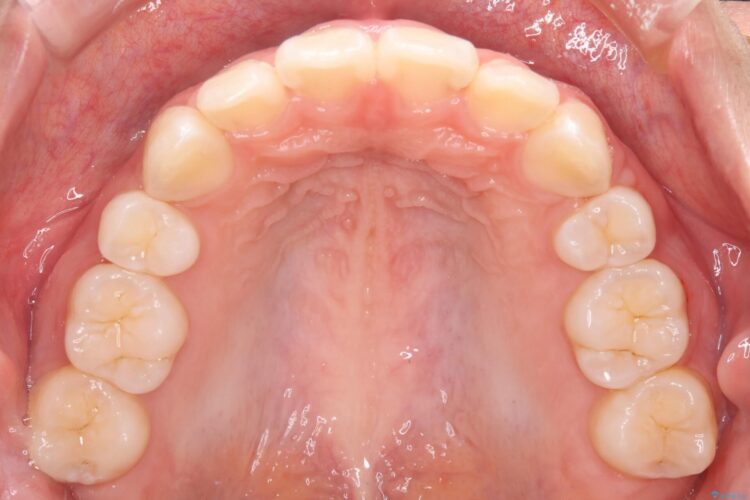

上下4番目の歯を抜歯してガタつきを改善しながら口元を下げる治療計画を立てました。

抜歯矯正で口元を下げたことで、Eラインが大変綺麗になりました。